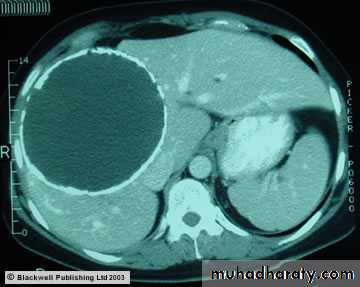

Abdominal CT Scan show. Large hepatic hydatid cyst

cestodes